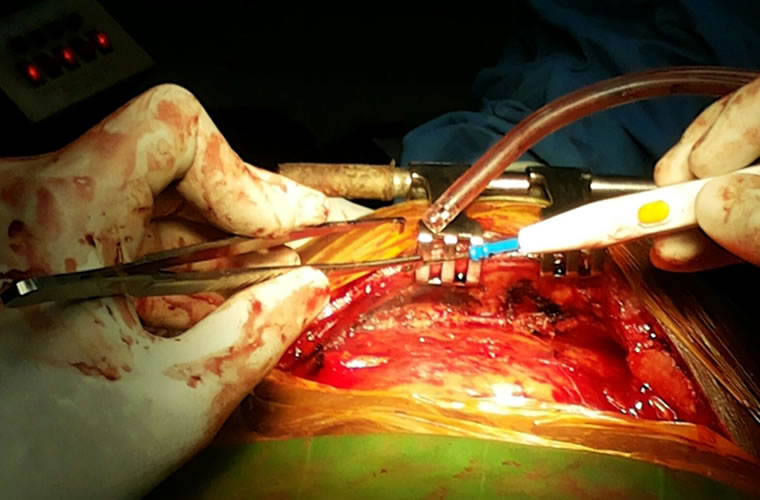

Dr.DineshShanmugaSundaram is specialized himself in each & every part of Cardiovascular & Thoracic Surgery both in Adult & Paediatric or Congenital Heart Diseases. He is both an ethical & academic surgeon,changed the trend in Cardiac Surgery to fast & safe level, as prolonged procedures in Cardiac Surgery increases postoperative complications. We aim at decreasing perioperative complications to the maximal level. Read More